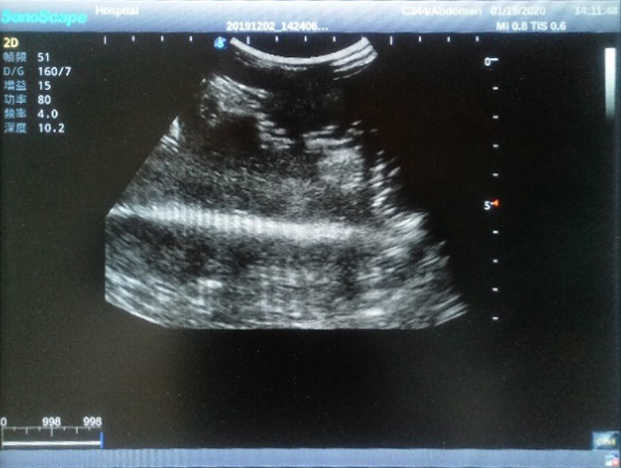

4) Biomimetic material allowing users to see clear and real normal tissues and space-occupying lesions that are hyperechoic, hypoechoic and isoechoic as they would see in the clinical environment